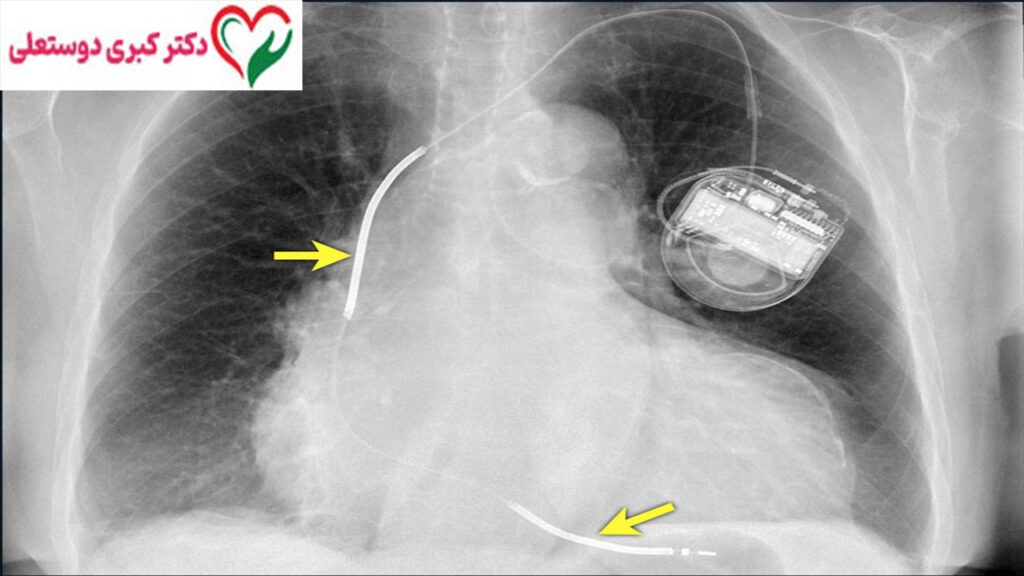

ICD (Implantable Cardioverter Defibrillator) دستگاهی الکترونیکی و کوچک است که در داخل بدن بیمار، معمولاً زیر پوست قفسه سینه یا زیر ترقوه، کاشته می‌شود. این دستگاه به‌طور مداوم ریتم قلب را پایش می‌کند و در صورت تشخیص ریتم‌های خطرناک، به‌صورت خودکار وارد عمل می‌شود.

ICD از سه بخش اصلی تشکیل شده است:

1. ژنراتور (باطری و مدار الکترونیکی)

2. الکترودها (سیم‌هایی که به قلب متصل می‌شوند)

3. نرم‌افزار هوشمند تشخیص ریتم قلب

مراحل کاشت ICD

مراحل کلی:

1. ایجاد برش کوچک زیر ترقوه

2. وارد کردن الکترودها به قلب از طریق ورید

3. اتصال الکترودها به ژنراتور

4. تست عملکرد دستگاه

5. بستن محل برش